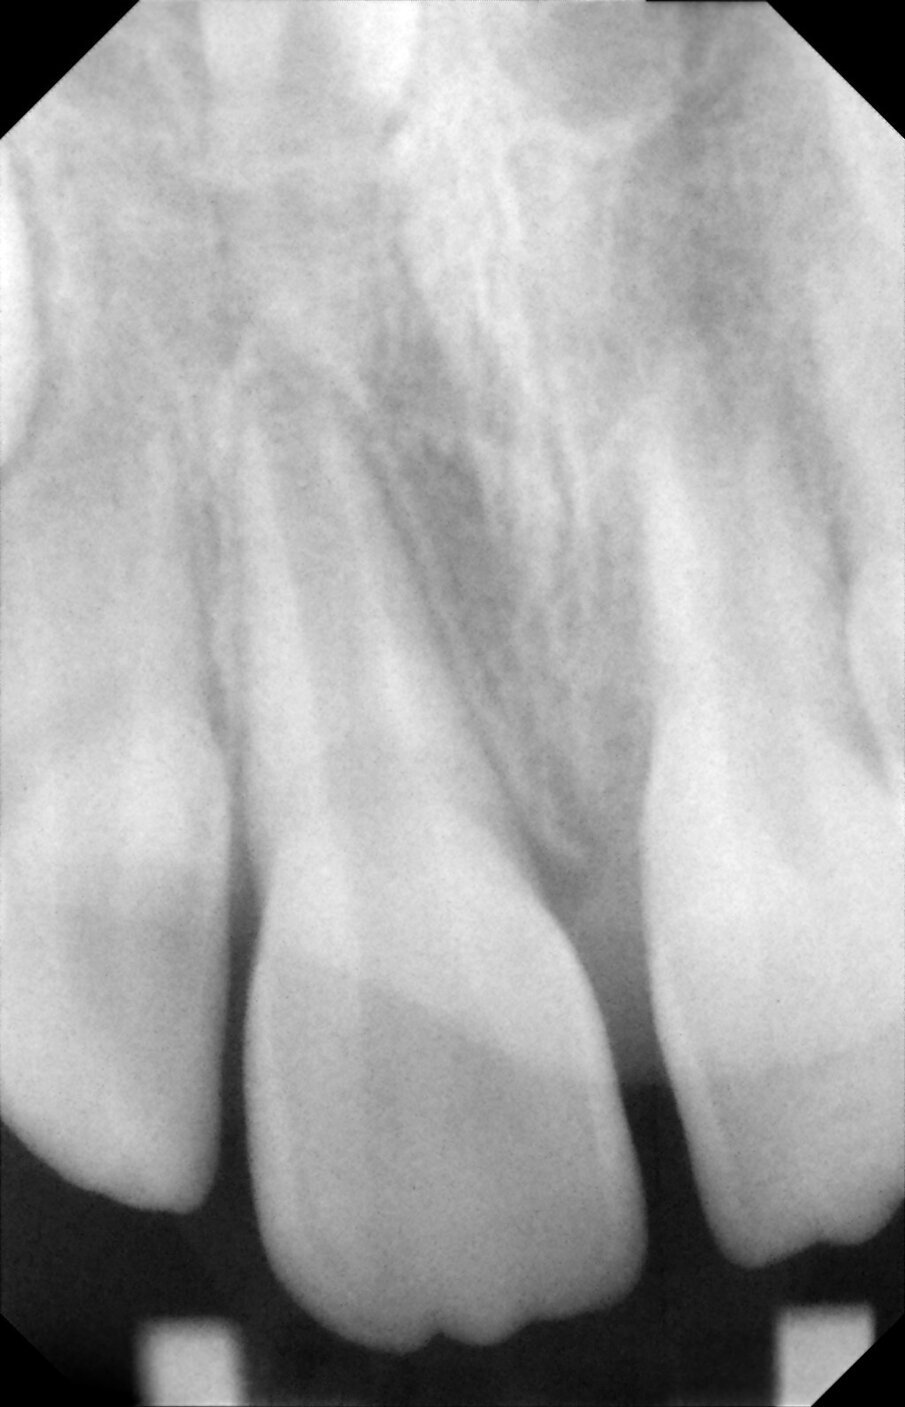

Periapical views of the upper maxillary incisors were obtained to rule out any root fractures (See Figures 4 a & b) revealed immature roots of teeth # 12, 11, 22, no root fractures and an inverted supernumerary apical to 11 and an empty socket of 21. There was no need for soft tissue radiographs as no tooth fragments were missing and the tooth was accounted for.

Figures 4a. Empty socket of 21 due to its avulsion. Notice the immature apices of 12, 11 and 22. In addition there was a supernumerary tooth/mesiodens

Figures 4b. Empy socket of 21 due to its avulsion. Notice the immature apices of 12, 11 and 22. In addition there was a supernumerary tooth/mesiodens